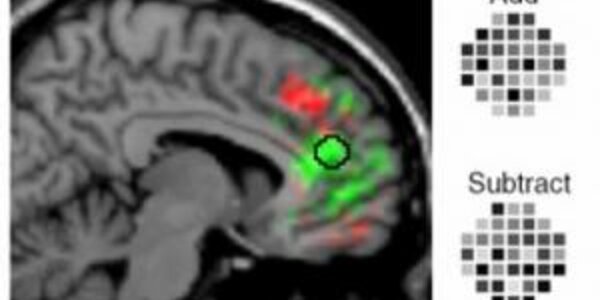

Revealing Secret Intentions In The Brain

Every day we plan numerous actions, such as to return a book to a friend or to make an appointment. How and where the brain stores these intentions has been revealed by John-Dylan Haynes from the Max Planck Institute for Human Cognitive and Brain Sciences, in cooperation with researchers from London and Tokyo. For the first time they were able to "read" participants' intentions out of their brain activity. This was made possible by a new combination of functional magnetic resonance imaging and sophisticated computer algorithms (Current Biology, 20th February 2007, online: 8th February).…